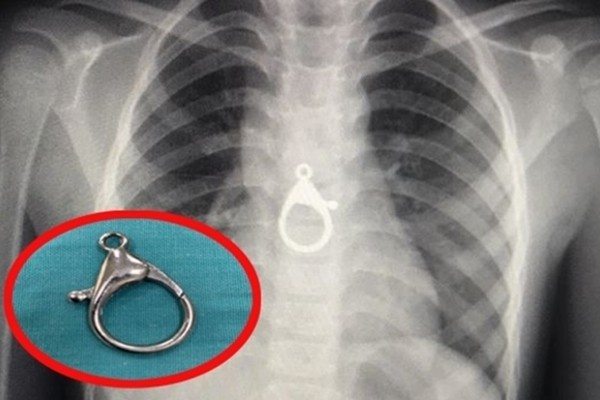

Gắp móc khóa xe khỏi vùng ngực của bé trai 6 tuổi

Hướng dẫn nuôi dạy con -  14/08/2020

Tối nay (13/8), bác sĩ Nguyễn Thanh Tiên, Trưởng khoa Tai Mũi Họng (BV Đa khoa Quảng Nam), cho biết, vừa gắp thành công chiếc móc khóa ra khỏi thực qu...